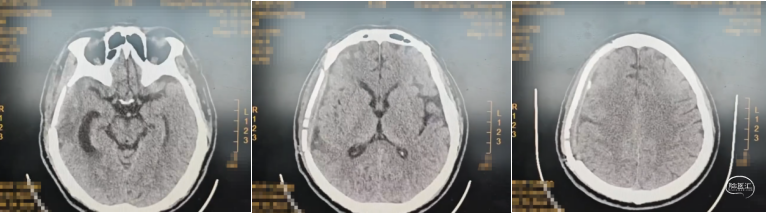

诊疗过程:急诊行开颅硬膜下血肿清除+脑挫裂伤病灶清除+去颅骨骨瓣减压,术后20天意识逐步转清,病情平稳后转康复科康复,术后两个半月再次住院行颅骨修补,患者意识清,言语清晰,肌力正常,骨窗略凹陷,切口愈合良好,术中行peek板修补,完整暴露骨窗缘,充分止血,将已塑形好颅骨固定系统1个(天津市康尔医疗器械有限公司;颅骨固定系统)及内固定板5个(天津市康尔医疗器械有限公司;聚醚醚酮颅骨内固定板)安放满意,脑组织未受压,以颅骨螺钉(天津市康尔医疗器械有限公司;颅骨螺钉)10枚,沿骨缘将颅骨固定系统固定于骨质上,确认固定牢靠外形满意,与骨窗贴合紧密无移位,术中行硬膜悬吊于peek板孔隙,皮下硅球引流,弹力绷带加压包扎,48小时后拔除引流管。

颅骨修补术后CT: